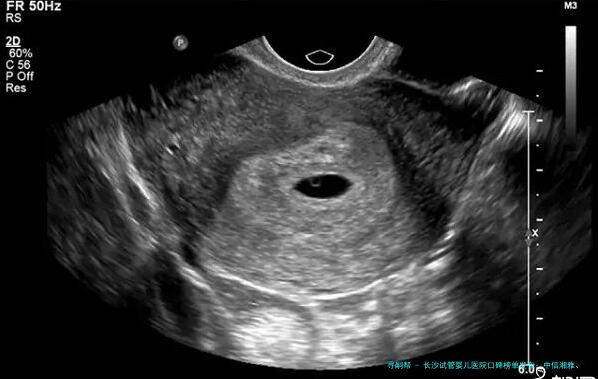

长沙试管婴儿医院口碑榜单发布:中信湘雅、湘雅医院等五家机构实力解析,附医生推荐与费用参考